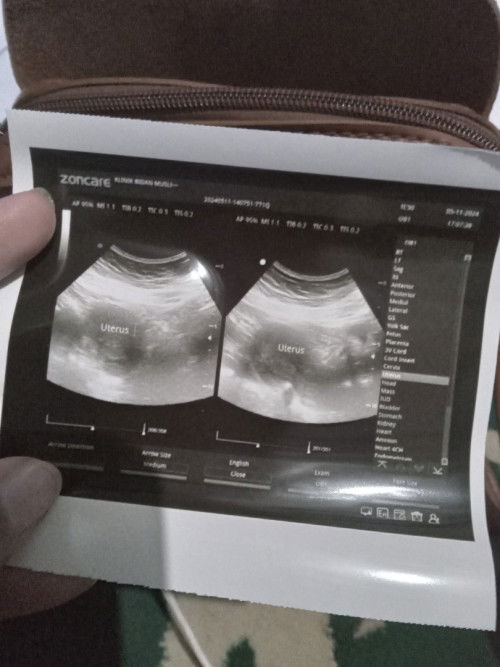

Kabar setelah pendarahan

Dari kemarin pendarahan spt haid, tadi sore langsung usg dan katanya kantung janin belom ada dan baru penebalan dinding rahim dan katanya bisa aja haid. Padahal sebelumnya testpack garis 2, kira kira ada yg pernah mengalami? #SeriusTanya #Sharing_dong_Bund #bantujawab